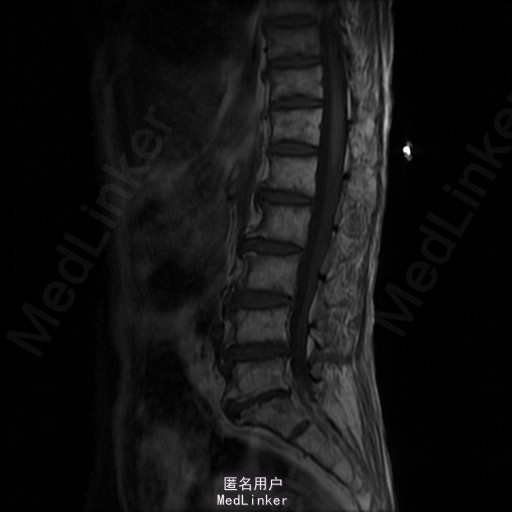

查体:左侧小腿外侧、足背感觉减退,右侧正常,双侧屈髋、伸膝、踝背伸肌肌力5级,左侧踇背伸、跖屈肌肌力4级,右侧踇背伸、跖屈肌肌力4-5级,双侧巴氏征阴性,直腿抬高试验左侧30°阳性,右侧阴性。 辅助检查: X-ray:腰椎退行性变,腰椎节段性性不稳 MR:腰椎间盘突出,腰3/4,4/5,腰4/5节段明显

诊断:腰椎椎管狭窄 处理: 1、完善相关辅助检查,明确诊断,有无手术指证; 2、完善手术评估,有无手术禁忌,手术风险及并发症; 3、在全麻下行腰椎后路减压,腰3/4左侧椎板减压,腰4/5椎间Cage植骨融合内固定术

随访 术后患者下肢麻木感觉较前好转,左侧踝背伸、跖屈肌力4级+,左侧肢体抬高试验阴性。术后MR检查减压彻底 讨论:1、腰椎椎管狭窄手术指证的把握,腰椎后路手术,腰椎椎间融合与椎板减压的选择? 2、术中探查如无明显间盘突出,以椎管骨性狭窄为主,可行腰椎后路椎板减压为主。